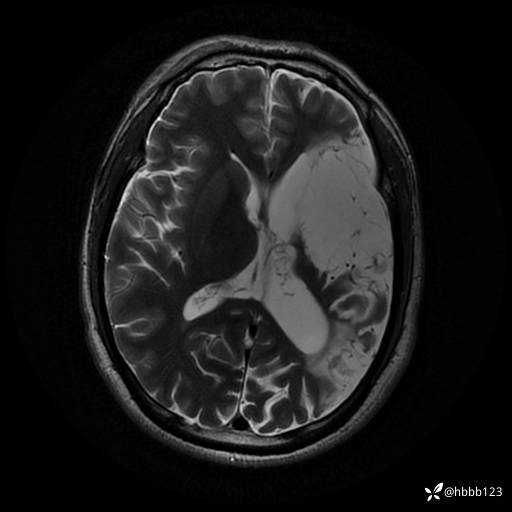

T2: